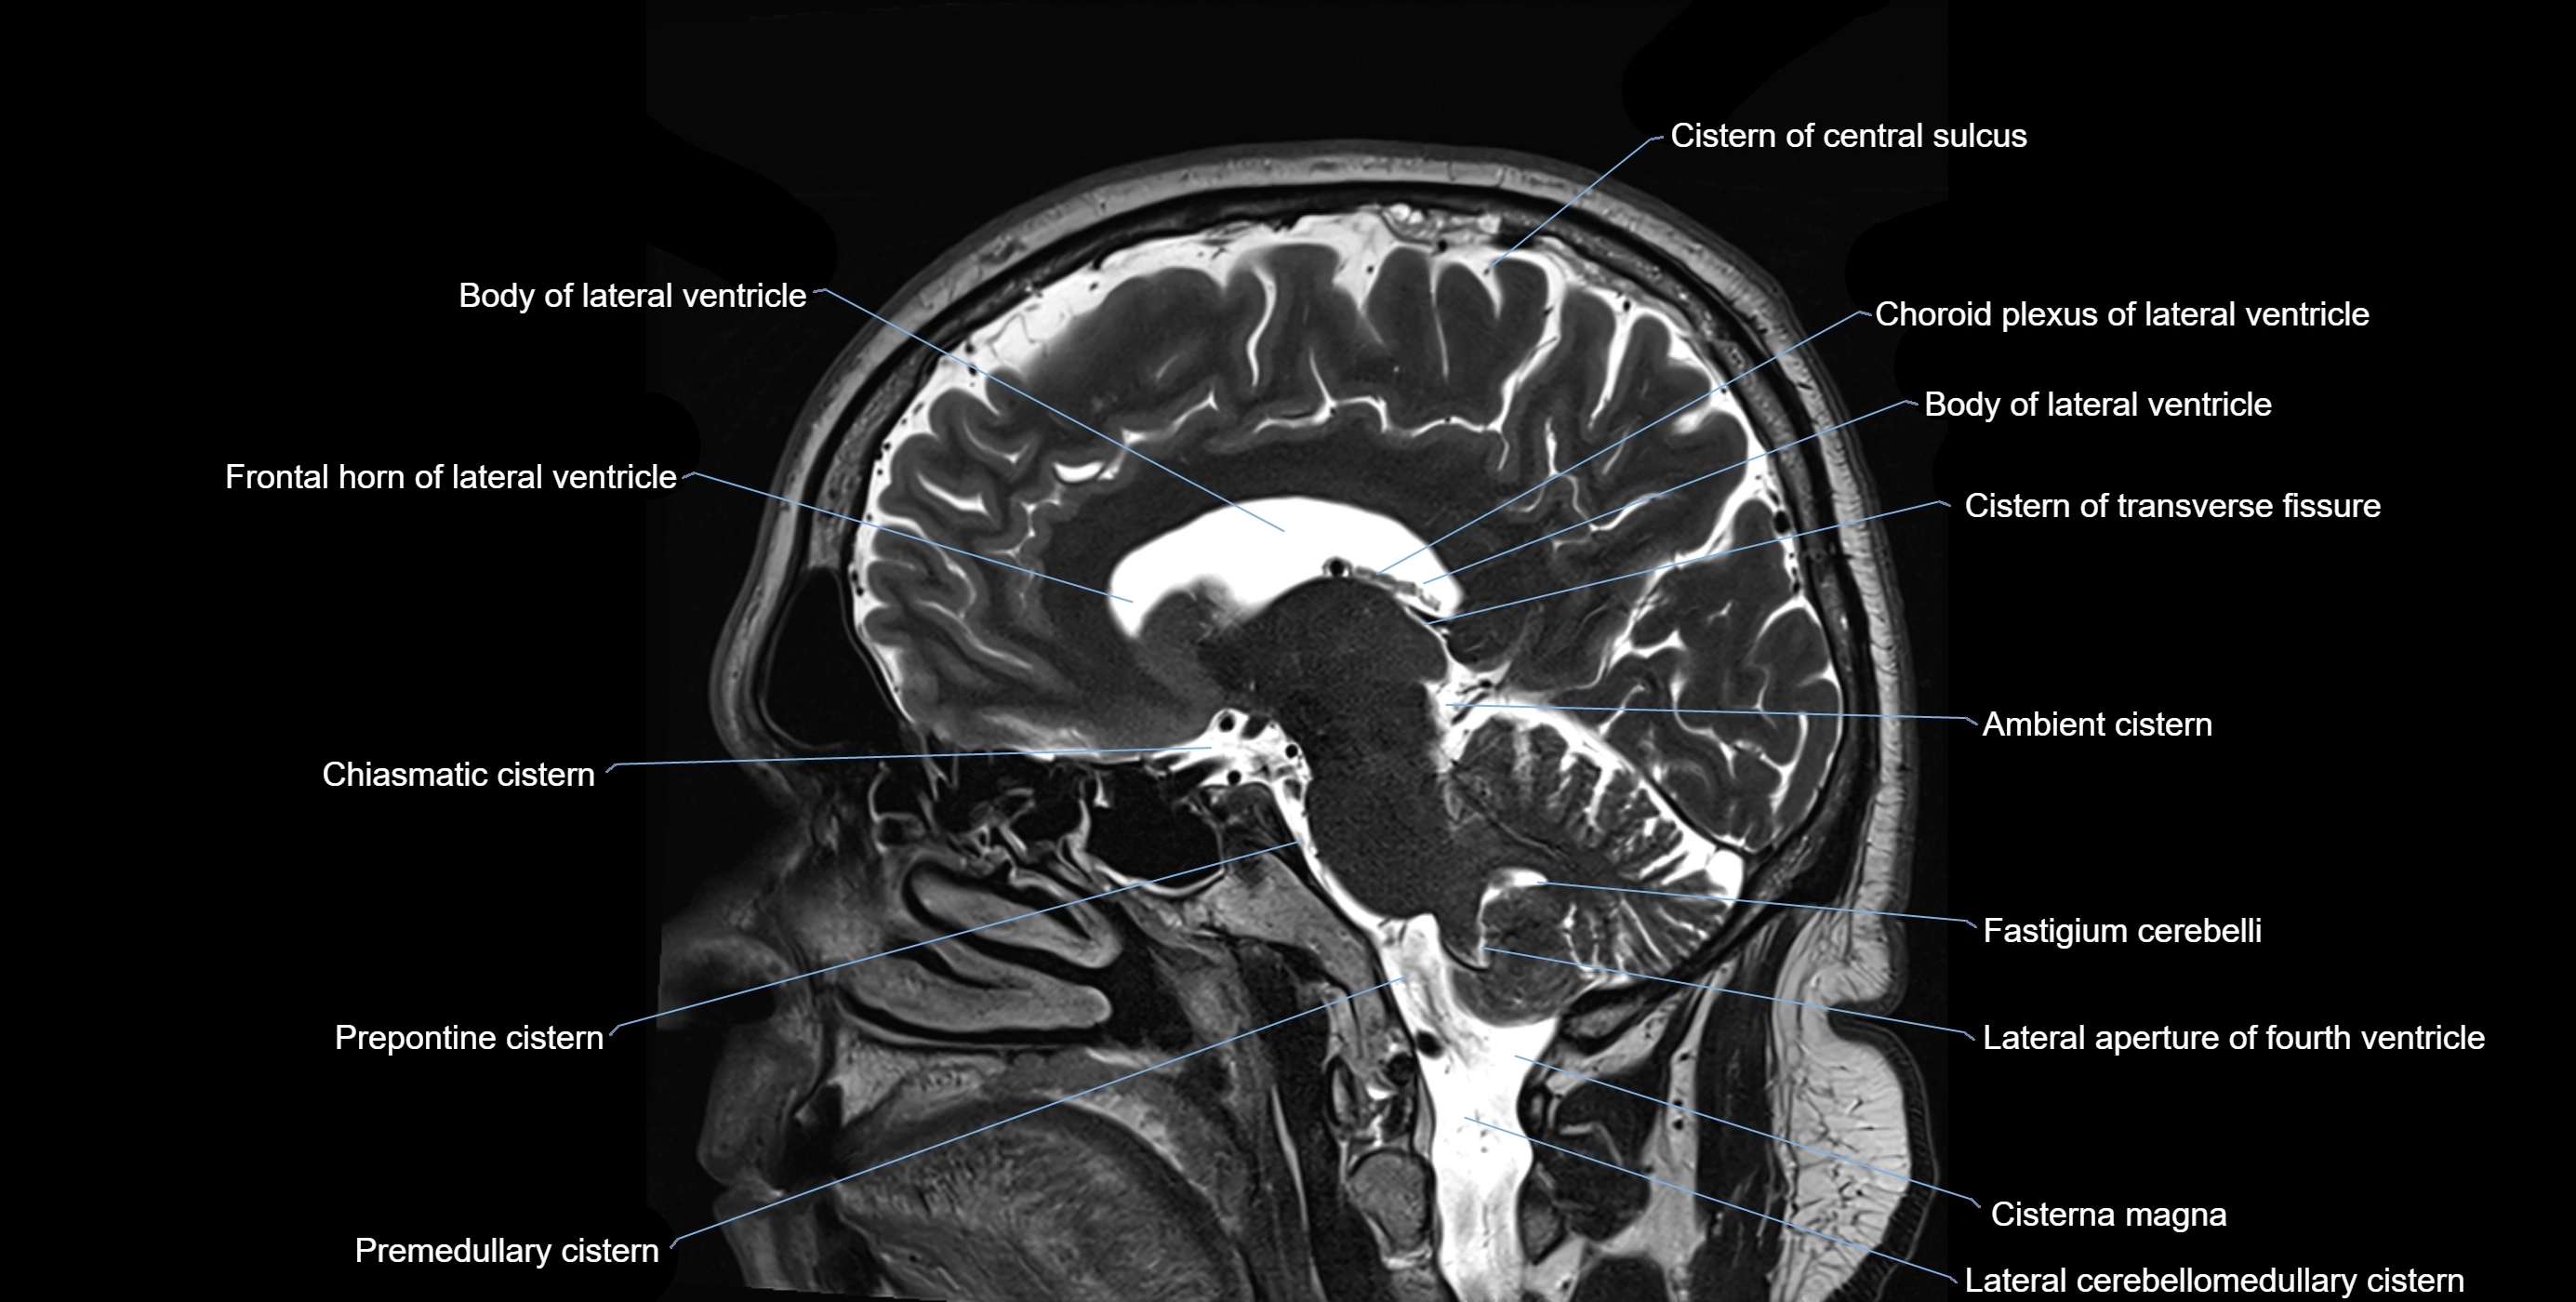

MRI images

image